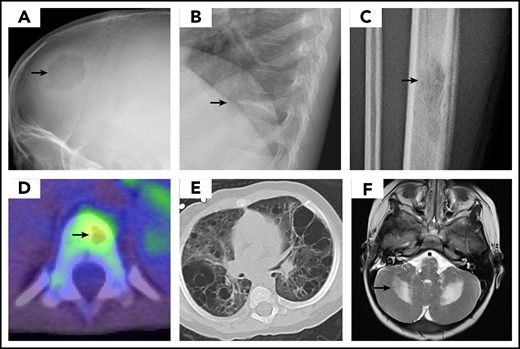

Most organs can be affected by LCH, and therefore a comprehensive evaluation is indicated.27 Symptoms and physical and laboratory examination should guide the extent of diagnostic studies; focus should be on assessing the number of systems and sites involved, and on the involvement of risk organs. Bone imaging studies reveal a lytic lesion without marginal sclerosis, with or without periosteal reaction. (Figure 2) Radio-isotope imaging is recommended to assess the number of bone lesions; fluorodeoxyglucose–positron emission tomography scans can be useful in defining the extent of the disease and the response to therapy.28,29 (Figure 2) The skull, including the skull base, is very commonly involved; typical locations include the bones of the orbit or the temporal bone (typically the mastoid). Involvement of the vertebral bodies is also common, and the presence of a vertebra plana is frequent. Pain and tumor formation in a localized area of bone is a very common presentation of LCH.

LCH imaging. Images demonstrate typical presentation of LCH lesions including (A) single skull lesion on X-ray, (B) vertebra plana on X-ray, (C) femur lesion on X-ray, (D) vertebral lesion on positron emission tomography/computed tomography scan, and (E) cystic lung disease on computed tomography scan. (F) Brain magnetic resonance imaging demonstrates T2 hyperintensity in cerebellum in LCH-associated neurodegeneration. (Courtesy of P. Campbell)

In children, lung involvement usually occurs in the context of multisystem disease, where it has been reported to occur in up to 35% of patients.40 Radiographic findings are typical for the presence of a reticulonodular pattern with bullae formation (Figure 2). In the absence of other risk organ involvement, pulmonary disease is not a predictor of adverse outcome.41-43 Isolated pulmonary involvement is a rare presentation that is almost exclusive of adults with a smoking habit.44

Neurodegenerative LCH (LCH-ND) is characterized by progressive radiologic and clinical abnormalities. As recently reviewed by Yeh et al,60 2 separate clinical forms are identified: LCH-associated abnormal CNS imaging (LACI), which includes asymptomatic patients with radiologic findings, and LCH-associated abnormal CNS symptoms (LACS), which describes patients with abnormal cognitive and psychological findings. LACI and LACS are associated with increased T2-weighted MRI signal in the dentate nucleus of the cerebellum, basal ganglia, and pons (Figure 2; Table 4).

The appearance of clinical and radiographic signs of LCH-ND can occur with the initial LCH diagnosis, although it commonly occurs years later.60,61,69 Symptoms may initially include tremors, abnormal reflexes, gait disturbance, motor spasticity, ataxia, dysarthria, dysphagia, behavioral changes, learning disorder, or psychiatric problems. Some patients develop a progressive cerebellar syndrome, with spastic tetraparesis, pseudobulbar palsy, and cognitive deterioration.60,61 Magnetic resonance imaging shows a characteristic infratentorial predilection, with symmetric abnormalities of the dentate nuclei and of the white matter of the cerebellum and pons (Figure 2; Table 4). Outside the infratentorial compartment, abnormalities of the basal ganglia, optic nerves, and tracts; dilatation of the Virchow-Robin spaces; or diffuse abnormalities of the hemispheric white matter consistent with leukoencephalopathy are also common.60,61 Serial imaging and neurocognitive evaluations are recommended when the disease is suspected.60,70